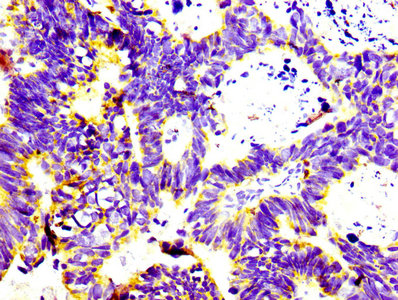

• IHC image of CSB-RA004956A0HU diluted at 1:100 and staining in paraffin-embedded human ovarian cancer performed on a Leica BondTM system. After dewaxing and hydration, antigen retrieval was mediated by high pressure in a citrate buffer (pH 6.0). Section was blocked with 10% normal goat serum 30min at RT. Then primary antibody (1% BSA) was incubated at 4°C overnight. The primary is detected by a biotinylated secondary antibody and visualized using an HRP conjugated SP system.